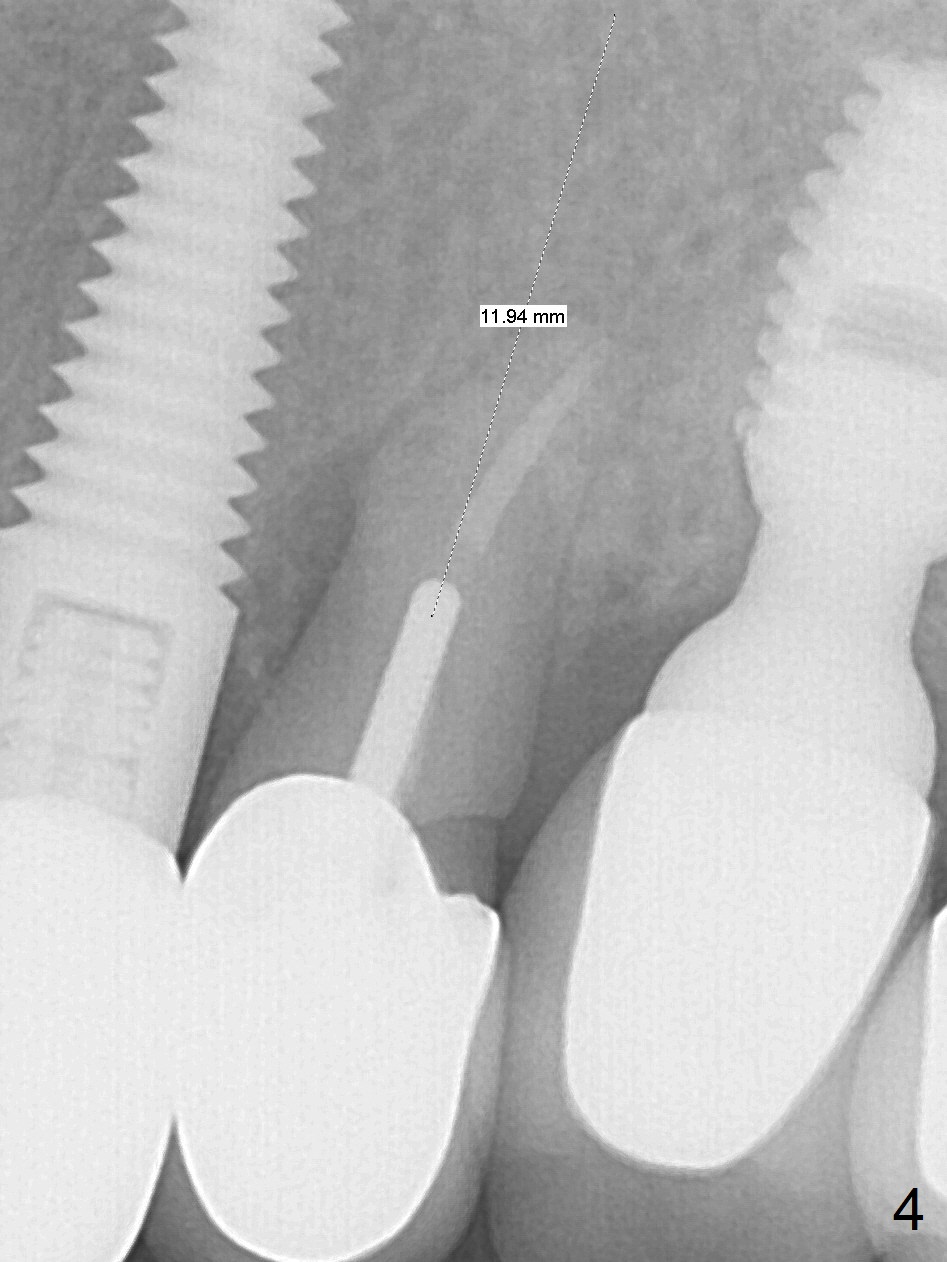

A 59-year-old woman has mild discomfort in the upper left quadrant, which is alleviated by salt water rinse. The buccal gingiva recedes at #13 with mesiobuccal swelling and deep pocket (Fig.1,3), corresponding to the mesial radiolucency (Fig.2 *). The tooth appears to have vertical fractured root, as related to the retention post. Since the root tip curves distal, the initial osteotomy (Fig.5 red) should be established in the mesioapical slope after extraction (black). Following initial entrance, the trajectory will be changed to the long axis of the space (Fig.6) with PA to be taken. Measure the depth of the buccal crest against the buccal, proximal and palatal gingival margins. Place an implant, the same as #12 (4.5x20 mm) unless the mesiobuccal defect is extremely large (UF).